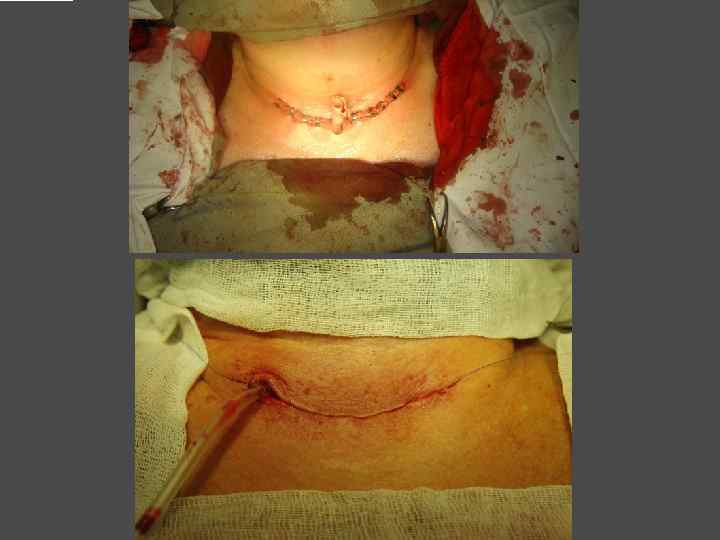

ХИРУРГИЧЕСКОЕ ЛЕЧЕНИЕ ЗОБА

ОСЛОЖНЕНИЯ ХИРУРГИЧЕСКОГО ЛЕЧЕНИЯ ►Поражение возвратного нерва, приводящее к параличу голосовой связки на стороне поражения, как следствие – изменение тембра голоса, сужение голосовой щели, затруднение дыхания. ► Кровотечение. ►Тиреотоксический криз. ► Гипопаратиреоз. ► Рецидив тиреотоксикоза. ► Формирование порочного рубца.

ВЕДЕНИЕ БОЛЬНЫХ ПОСЛЕ ХИРУРГИЧЕСКОГО ЛЕЧЕНИЯ ► Заместительная терапия тиреоидными гормонами. ► Контроль уровня ТТГ и Т 4 своб через 2 месяца после операции. ► УЗИ передней поверхности шеи при наличии показаний.